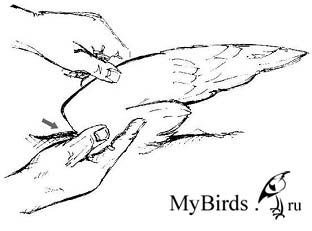

Консервативная фиксация должна проводиться только на одной стороне, и используемый для повязки материал не должен повредить перья. Наиболее подходящими являются самоклеящиеся повязки. Неповрежденное оперение для птицы столь же жизненно важно, как и целостный скелет. Свою эффективность доказала крестообразная повязка (см. рисунки). После удаления повязки птицу необходимо несколько дней тренировать, чтобы укрепить ее мышцы. С этой целью ее можно заставлять каждый день карабкаться вверх с одновременным взмахиванием крыльев или поощрять ее упражняться на полу. Не рекомендуется разрешать птице летать в помещении, т.к. стрижи развивают высокую скорость за короткое расстояние, и птица может легко причинить себе вред.

Крыло расположено в физиологическом положении. Чувствительную к давлению растянутую кожу крыла (показано стрелкой) необходимо осторожно удерживать в пальцах. Рисунок: C. Haupt

Эластичная повязка накладывается снизу вверх вокруг плечевой кости, затем через плечевой сустав и вокруг запястья. Рисунок: C. Haupt

Повязка располагается дорсально через крыло, снова перетягивается крестообразно снизу и вдоль под плечевой костью. Рисунок: C. Haupt